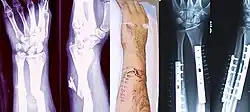

Fraktur des Armes (Armbruch)